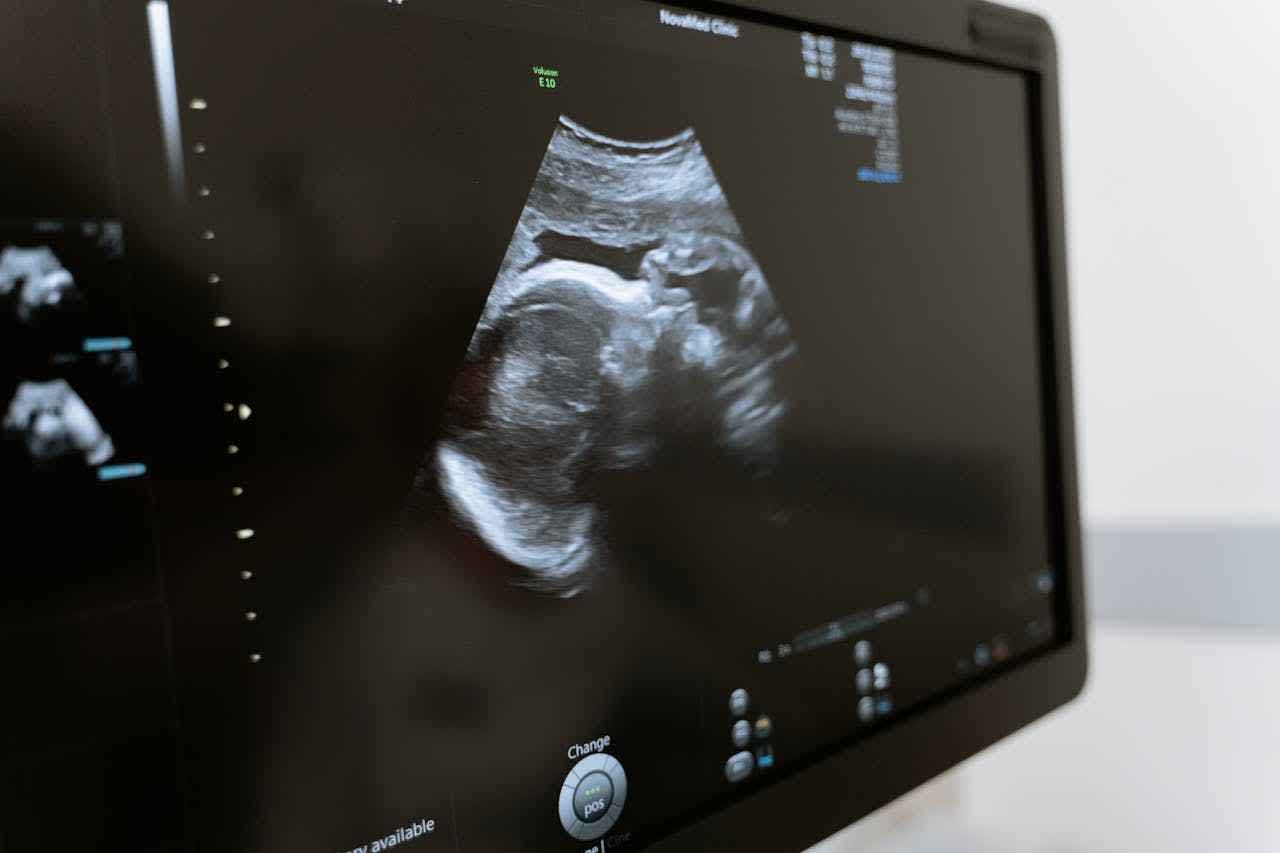

在婦產科,醫生會使用超音波檢查來確認胎兒的狀況和懷孕週數。這個步驟非常重要,因為懷孕週數會影響後續可以選擇的處理方式。以下是一些常見的情況:

(2)盡快到婦產科檢查胎兒狀況與懷孕週數

一旦確認懷孕,就應該盡快到婦產科接受專業的檢查。醫生會使用超音波評估胎兒的健康狀況,並確定具體的懷孕週數。這些資訊對於後續選擇適合的處理方式非常重要。及早發現問題,就能及時採取最適當的措施,確保自己的健康與安全。